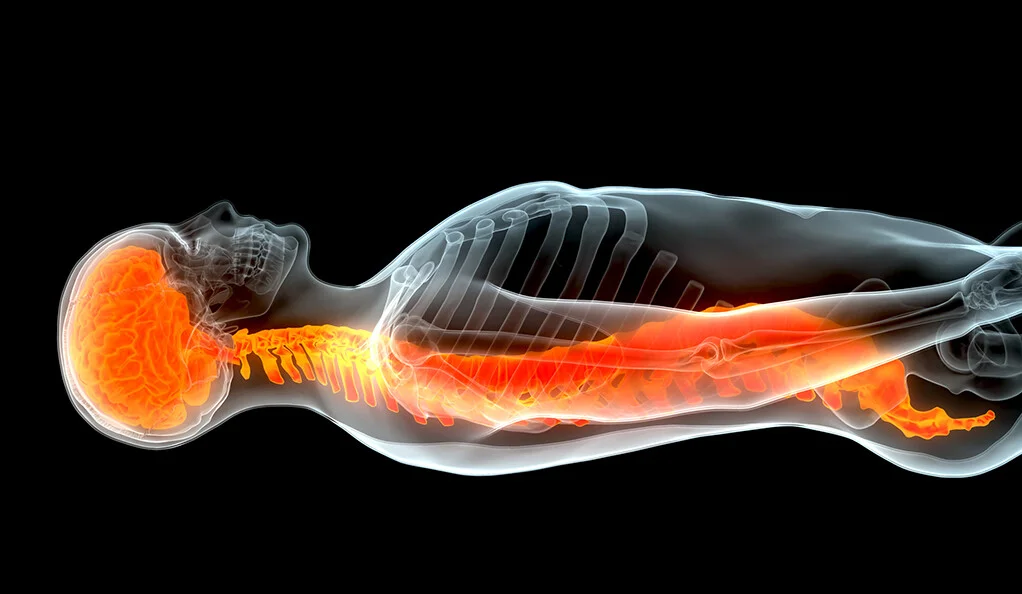

脊髓損傷患者靜脈注射骨髓干細胞可顯著改善運動功能。

耶魯大學和日本的研究人員在《臨床神經病學和神經外科雜志》上發表報告稱,脊髓損傷患者靜脈注射骨髓干細胞 (MSC) 可以顯著改善運動功能。?

研究人員報告說,超過一半的患者在注射干細胞后幾周內觀察到關鍵功能(例如行走或使用雙手的能力)的顯著改善。沒有報告明顯的副作用。

在干細胞植入前幾周,患者遭受了非穿透性脊髓損傷,許多情況下是由于跌倒或輕微創傷造成的。他們的癥狀包括運動功能和協調性喪失、感覺喪失以及腸道和膀胱功能障礙。干細胞是從患者自己的骨髓中通過培養方案制備的,該培養方案在專門的細胞處理中心花費了幾周的時間。在該系列中,細胞通過靜脈注射,每位患者作為自己的對照。結果不是盲法,也沒有安慰劑對照。